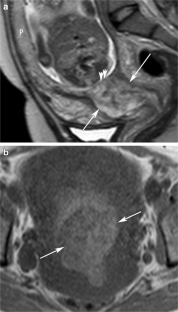

Fig. 2